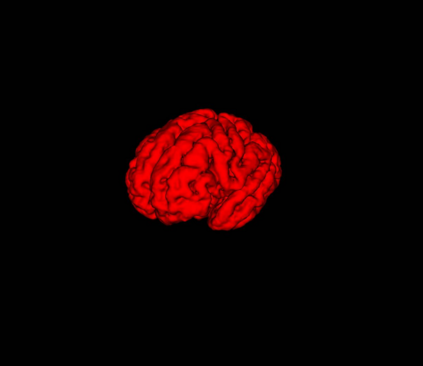

Fetal cortical plate segmentation is essential in quantitative analysis of fetal brain maturation and cortical folding. Manual segmentation of the cortical plate, or manual refinement of automatic segmentations is tedious and time-consuming. Automatic segmentation of the cortical plate, on the other hand, is challenged by the relatively low resolution of the reconstructed fetal brain MRI scans compared to the thin structure of the cortical plate, partial voluming, and the wide range of variations in the morphology of the cortical plate as the brain matures during gestation. To reduce the burden of manual refinement of segmentations, we have developed a new and powerful deep learning segmentation method. Our method exploits new deep attentive modules with mixed kernel convolutions within a fully convolutional neural network architecture that utilizes deep supervision and residual connections. We evaluated our method quantitatively based on several performance measures and expert evaluations. Results show that our method outperforms several state-of-the-art deep models for segmentation, as well as a state-of-the-art multi-atlas segmentation technique. We achieved average Dice similarity coefficient of 0.87, average Hausdorff distance of 0.96 mm, and average symmetric surface difference of 0.28 mm on reconstructed fetal brain MRI scans of fetuses scanned in the gestational age range of 16 to 39 weeks. With a computation time of less than 1 minute per fetal brain, our method can facilitate and accelerate large-scale studies on normal and altered fetal brain cortical maturation and folding.